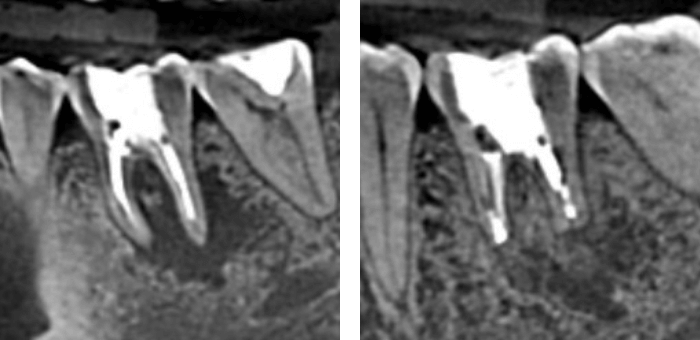

レントゲン写真

根の先に病変が見られた歯を、顕微鏡下で感染源を除去・封鎖。

術後に骨の再生を確認しました。